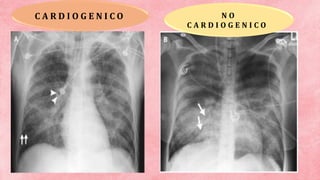

DIAGNO STICO RADIOGRAF ICO • Cardiomegalia • Redistribución vascular en lóbulos superiores • Ensanchamiento de la opacidad del pedículo vascular hiliar • Opacidad con infiltrado parahiliar “alas de mariposa” • Líneas Kerley HALLAZGOS RADIOGRAFICOS

C A RD I O G E N I C O N O C A R D I O G E N I C O